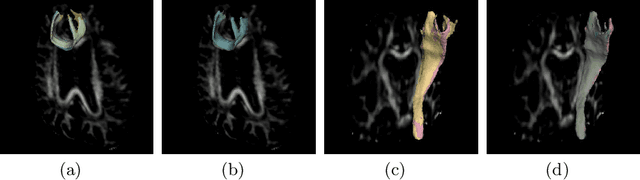

Abstract:Tract-specific diffusion measures, as derived from brain diffusion MRI, have been linked to white matter tract structural integrity and neurodegeneration. As a consequence, there is a large interest in the automatic segmentation of white matter tract in diffusion tensor MRI data. Methods based on the tractography are popular for white matter tract segmentation. However, because of the limited consistency and long processing time, such methods may not be suitable for clinical practice. We therefore developed a novel convolutional neural network based method to directly segment white matter tract trained on a low-resolution dataset of 9149 DTI images. The method is optimized on input, loss function and network architecture selections. We evaluated both segmentation accuracy and reproducibility, and reproducibility of determining tract-specific diffusion measures. The reproducibility of the method is higher than that of the reference standard and the determined diffusion measures are consistent. Therefore, we expect our method to be applicable in clinical practice and in longitudinal analysis of white matter microstructure.